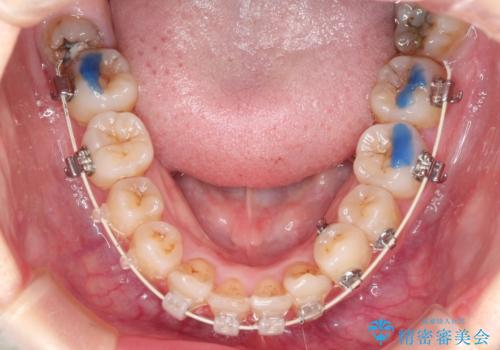

- 審美装置(ブラケット:白/ワイヤー:白)

初診時の歯並びの状態としては、上下ともに前歯部の中等度のがたつきがあり、下の前歯は本来生えるはずの歯が2本生まれつき欠損している状態でした。

抜歯ありワイヤー矯正にて治療を行い、抜歯する歯に関しては虫歯で抜歯が必要な部分を有効活用することで、健康な歯を保存するように努めました。

噛み合わせが深い過蓋咬合という状態でもあったため、下の歯の装置をつけたり、嚙み合わせを上げる(下の歯が見える状態にする)ことにたいへんに苦労した症例でした。